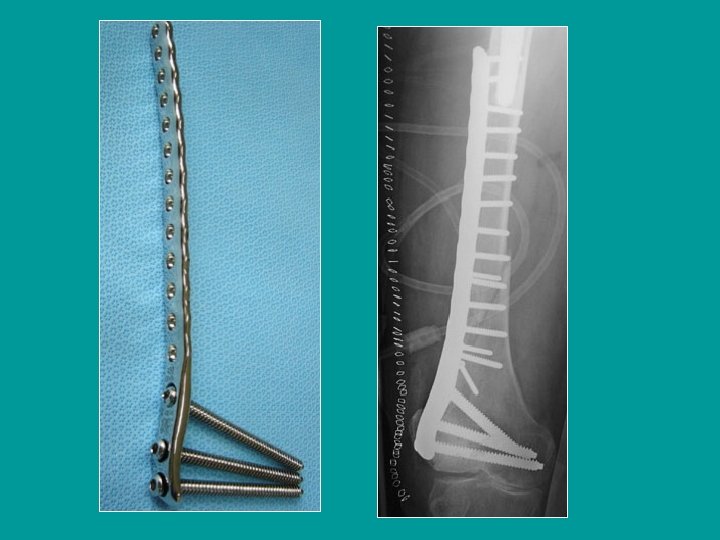

Osteosíntesis de las fracturas distales del fémur Clavo-placa AO Placas simples con tornillos

Osteosíntesis de las fracturas distales del fémur Tornillo-placa de Judet

Fracturas conminutivas Clavo-placa AO Placas en puente sobre la conminución

Instalación de un tornillo-placa de Judet

Placa con tornillos (clásicos)

Colocación de una placa de Chirón